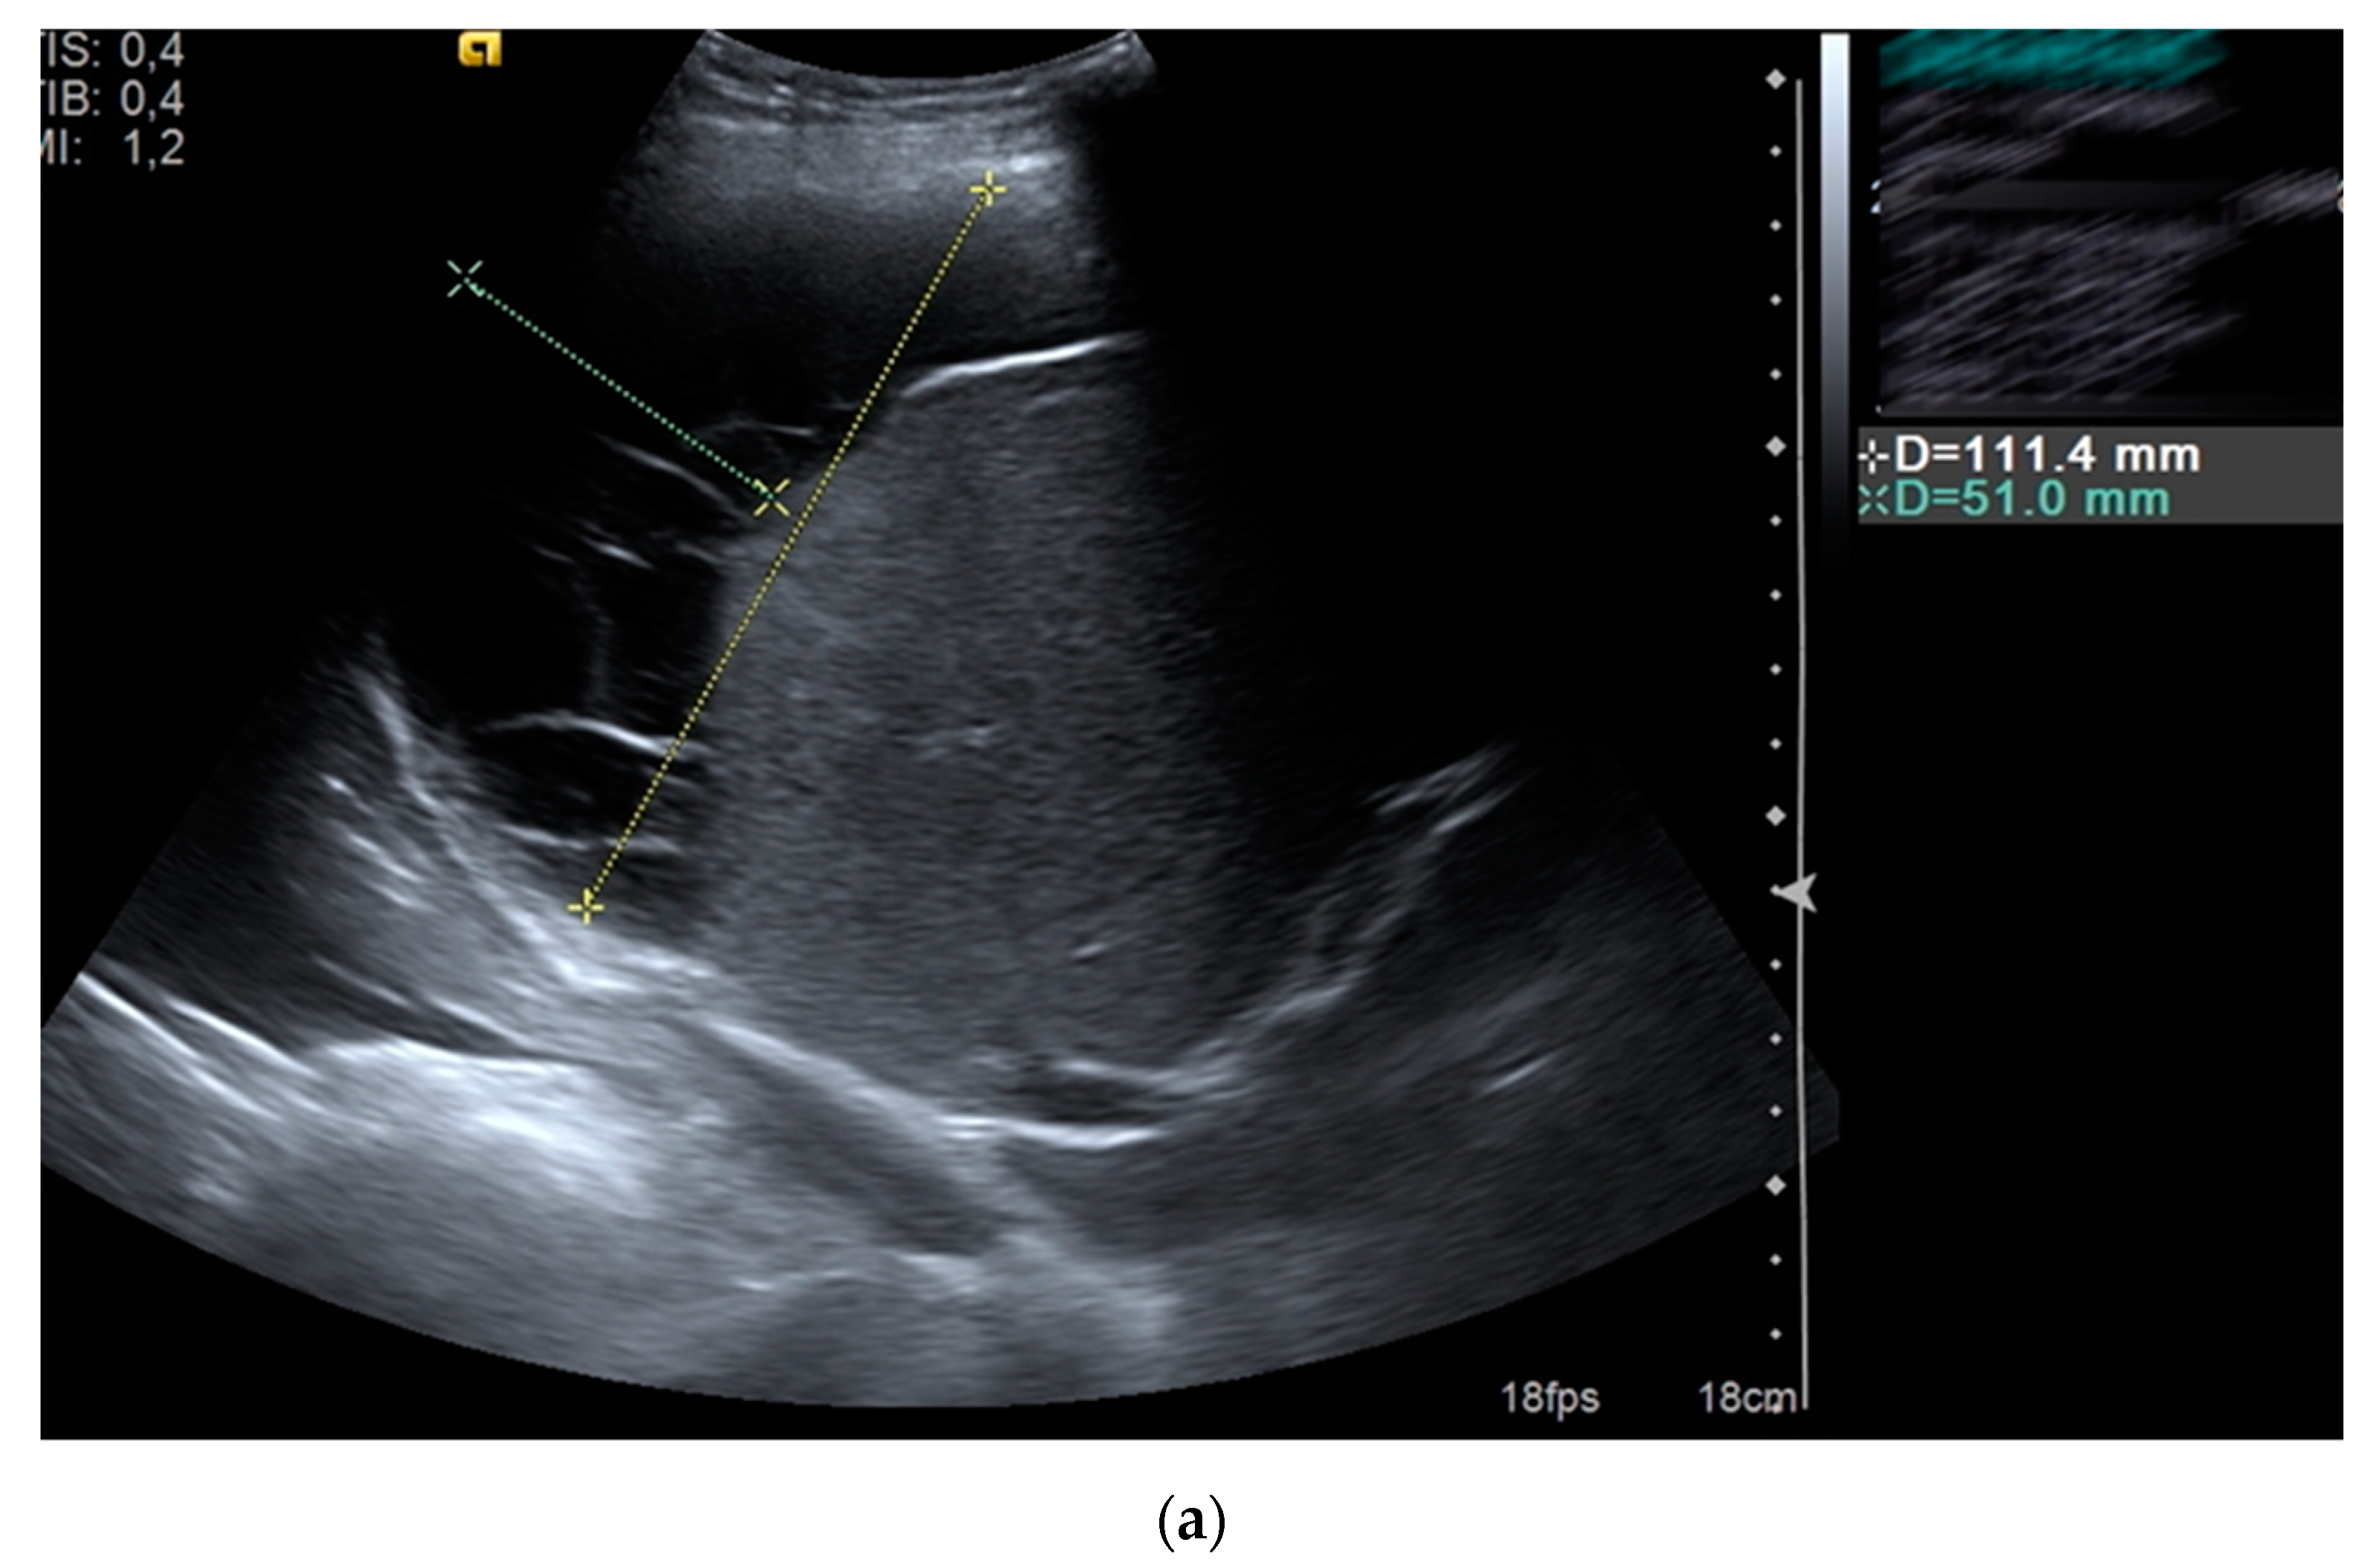

| Collection size (mm) | 88.26 ± 30.85 (40–200) |